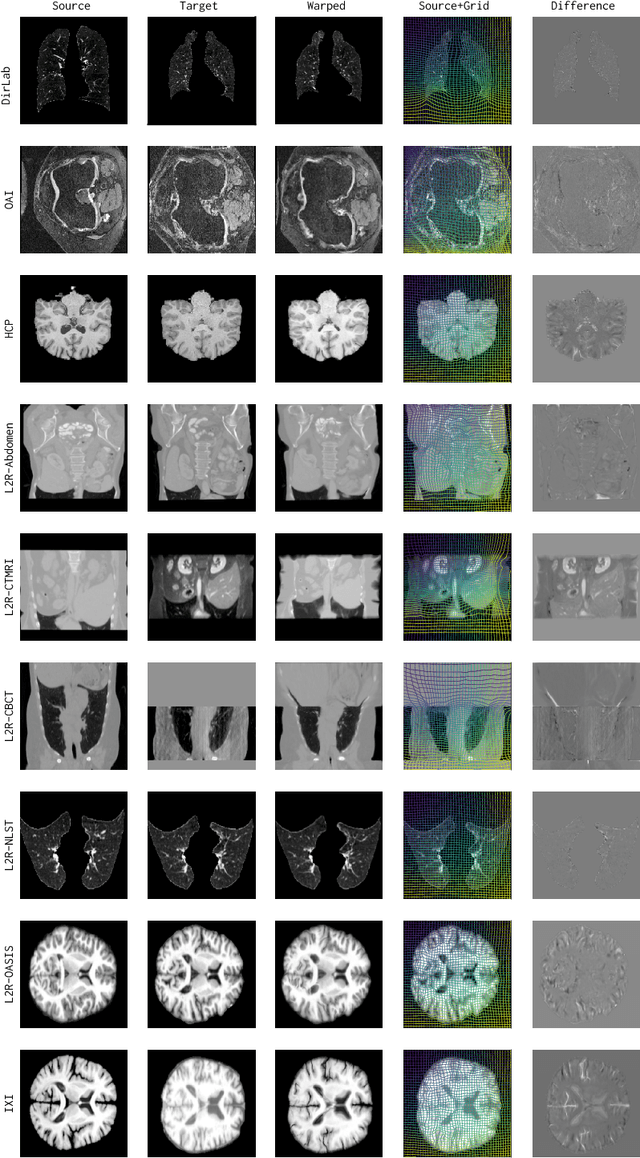

Abstract:Modern medical image registration approaches predict deformations using deep networks. These approaches achieve state-of-the-art (SOTA) registration accuracy and are generally fast. However, deep learning (DL) approaches are, in contrast to conventional non-deep-learning-based approaches, anatomy-specific. Recently, a universal deep registration approach, uniGradICON, has been proposed. However, uniGradICON focuses on monomodal image registration. In this work, we therefore develop multiGradICON as a first step towards universal *multimodal* medical image registration. Specifically, we show that 1) we can train a DL registration model that is suitable for monomodal *and* multimodal registration; 2) loss function randomization can increase multimodal registration accuracy; and 3) training a model with multimodal data helps multimodal generalization. Our code and the multiGradICON model are available at https://github.com/uncbiag/uniGradICON.

Abstract:Image registration estimates spatial correspondences between a pair of images. These estimates are typically obtained via numerical optimization or regression by a deep network. A desirable property of such estimators is that a correspondence estimate (e.g., the true oracle correspondence) for an image pair is maintained under deformations of the input images. Formally, the estimator should be equivariant to a desired class of image transformations. In this work, we present careful analyses of the desired equivariance properties in the context of multi-step deep registration networks. Based on these analyses we 1) introduce the notions of $[U,U]$ equivariance (network equivariance to the same deformations of the input images) and $[W,U]$ equivariance (where input images can undergo different deformations); we 2) show that in a suitable multi-step registration setup it is sufficient for overall $[W,U]$ equivariance if the first step has $[W,U]$ equivariance and all others have $[U,U]$ equivariance; we 3) show that common displacement-predicting networks only exhibit $[U,U]$ equivariance to translations instead of the more powerful $[W,U]$ equivariance; and we 4) show how to achieve multi-step $[W,U]$ equivariance via a coordinate-attention mechanism combined with displacement-predicting refinement layers (CARL). Overall, our approach obtains excellent practical registration performance on several 3D medical image registration tasks and outperforms existing unsupervised approaches for the challenging problem of abdomen registration.

Abstract:Conventional medical image registration approaches directly optimize over the parameters of a transformation model. These approaches have been highly successful and are used generically for registrations of different anatomical regions. Recent deep registration networks are incredibly fast and accurate but are only trained for specific tasks. Hence, they are no longer generic registration approaches. We therefore propose uniGradICON, a first step toward a foundation model for registration providing 1) great performance \emph{across} multiple datasets which is not feasible for current learning-based registration methods, 2) zero-shot capabilities for new registration tasks suitable for different acquisitions, anatomical regions, and modalities compared to the training dataset, and 3) a strong initialization for finetuning on out-of-distribution registration tasks. UniGradICON unifies the speed and accuracy benefits of learning-based registration algorithms with the generic applicability of conventional non-deep-learning approaches. We extensively trained and evaluated uniGradICON on twelve different public datasets. Our code and the uniGradICON model are available at https://github.com/uncbiag/uniGradICON.